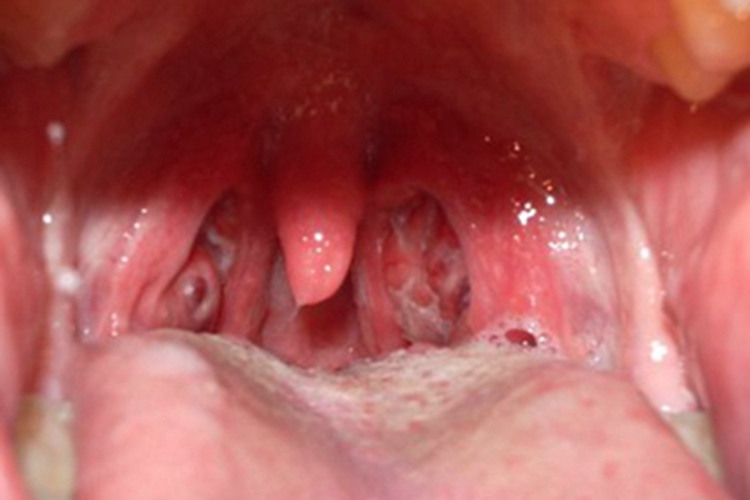

急性咽炎:急性咽炎可导致患者咽部弥漫性充血、红肿,表面可有黄白色点状渗出物,患者自觉疼痛。

慢性咽炎:慢性肥厚性咽炎患者咽部轻微红肿,且有很多黏稠的黄白色分泌物附着于咽后壁,导致患者总是感觉咽部有异物感、痒感、干燥感等,晨起时会出现咳嗽并伴有恶心。